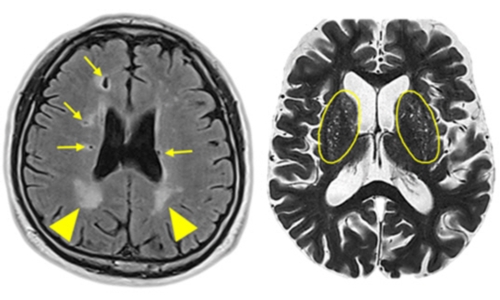

뇌경색 원인은 동맥경화증으로 시작합니다. 병이 든 혈관 어떤 곳에든 핏덩어리가 생겨나면 심장에서 뇌로 흐르는 혈액의 흐름을 방해하게 됩니다. 만약 핏덩어리가 내경동맥이나 뇌혈관을 막게 되면 치명적인 뇌 손상을 입을 수 있습니다. 이렇듯 갑자기 혈관을 막는 경우도 있으나, 혈전에 의하여 점차 혈관 너비가 좁아지면서 허혈성 뇌졸중이 유발되는 경우도 있습니다.

뇌경색 초기증상으로는 어눌한 발음과 같은 언어 장애, 물건을 들고 있다가 떨어뜨릴 만큼 팔이나 다리에 힘이 빠지는 감각 이상, 한쪽에 마비가 오는 얼굴 감각이상, 극심한 두통, 어지럼증 등이 있습니다. 이러한 증상이 보인다면 뇌경색을 의심해볼 수 있습니다. 급성 뇌경색이 찾아오는 경우에는 특정한 뇌경색 전조증상이 나타납니다.극심한 두통이 있으며 동시에 평소와 다르게 말이 어눌하고 의사소통이 잘되지 않습니다. 이 경우 지체 없이 신속히 의료기관을 찾아야 합니다. 또한 팔다리의 한 쪽에 마비 증세가 있거나 눈 시력이 별 이유 없이 갑자기 저하되는 경우, 다리가 저리며 보행이 어려운 것 또한 뇌경색 증상으로 의심해 볼 수 있는 모습입니다.

앞서 설명한 뇌경색 전조증상이 나타났다가 5-10분 뒤에 아무 일이 없었다는 듯 평소의 모습으로 돌아올 수 있습니다. 특히 고령이거나 당뇨, 고혈압, 고지혈증과 같은 기저질환을 가진 경우, 흡연, 과음, 과로 등의 요인이 있는 경우에는 뇌경색 초기증상을 숙지하고 증상이 나타나면 신속하게 병원을 찾아 검사와 진단을 통해 적절한 치료를 받아야 뇌경색의 악화와 후유증을 최소화시킬 수 있습니다.